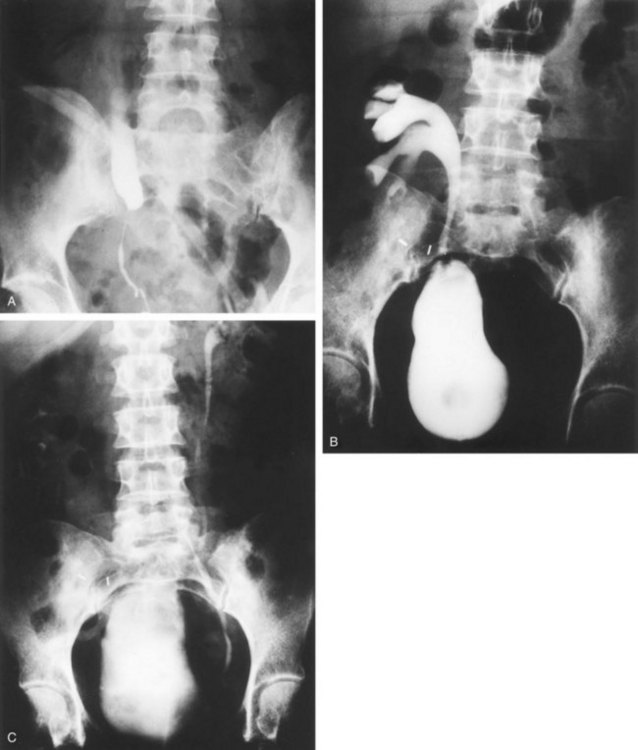

The indications to intervene for any patient with UPJ obstruction include the presence of symptoms, progressive or overall impairment of renal function, development of upper tract stones or infection, or, rarely, causal hypertension. Historically, a percutaneous approach for definitive management of UPJ obstruction was offered only to those patients undergoing percutaneous removal of associated stones or to those who had previously failed open pyeloplasty. However, encouraging results ultimately led many centers to offer percutaneous endopyelotomy as primary therapy for almost any patient with UPJ obstruction. Even with the acceptance of laparoscopic pyeloplasty, percutaneous endopyelotomy is also appropriate for those patients with UPJ obstruction and concomitant pyelocalyceal stones, which can then be managed simultaneously. Contraindications to a percutaneous endopyelotomy are similar to the contraindications to any endourologic approach and include a long segment (>2 cm) of obstruction, active infection, or untreated coagulopathy. Whereas the impact of crossing vessels is controversial, the mere presence of crossing vessels is not a contraindication to an endopyelotomy (Motola et al, 1993b; Nakada et al, 1998; Lam et al, 2003b). However, significant entanglement of the UPJ by crossing vessels can occasionally be identified and this may render any endourologic approach unsuccessful. When such entanglement is suggested by intravenous or retrograde pyelography (Fig. 41–7), it can be reliably verified using three-dimensional helical CT (Kumon et al, 1997).

In the original descriptions of the technique both from the Institute of Urology in London (Ramsay et al, 1984) and from Long Island Jewish Hospital in New York (Badlani et al, 1986), the endopyelotomy was performed using a cold knife technique under direct vision. With one or two wires in place across the UPJ, a direct vision “endopyelotome” is used. This hook-shaped cold knife may be used to completely incise the UPJ in a full-thickness manner, from the ureteral lumen to periureteral and peripelvic fat (Fig. 41–8). Rigorous anatomic studies have shown the incision should generally be made laterally because this is the location devoid of crossing vessels (Sampaio, 1998). However, in cases of high insertion, the incision should instead “marsupialize” the proximal ureter into the renal pelvis, such that an anterior or posterior incision may be required (Fig. 41–9). When such incisions are done under direct vision, any crossing vessel can be directly visualized and avoided. In addition to the endopyelotome, the holmium laser or the cutting balloon catheter may also be used to perform an antegrade endopyelotomy.

Figure 41–9 A, Retrograde study in this patient with left ureteropelvic junction obstruction reveals a “high insertion” of the left ureter. B, CT scan in this same patient reveals the ureter inserting on the anatomically anterior aspect of the renal pelvis. A marsupializing incision must be made in a true posterior direction from the ureter into the renal pelvis.